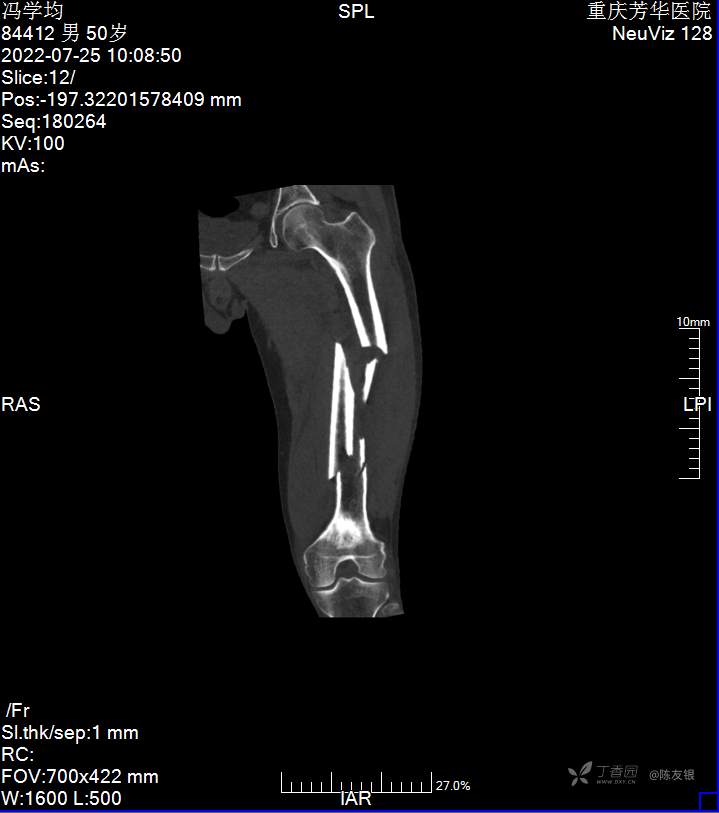

患者冯某,男性,50岁,车祸致全身多处肿痛、活动受限1小时于2022年7月24日入院。肇事司机诉今日8时左右在渝北区朝阳河大桥上与前车,一辆环卫作业车发生追尾碰撞,导致患者受伤,伤后意识尚清楚,诉全身多处疼痛,伤后无昏迷,无恶心呕吐 ,无畏寒发热,心慌心悸等不适,由120立即送至我院,门诊行头胸腹及左大腿CT提示:1、颅内未见明显挫裂伤。2、左侧颧弓粉碎性骨折,骨折线累及颞颌关节窝。3、颈椎骨质增生,项韧带钙化。4、颈7左侧横突骨折;颈椎未见明显骨折征象;颈部皮下广泛积气。5、左肺上下叶肺挫伤;左侧血气胸,左肺压缩约25%;右侧胸腔少量积液。6、左侧锁骨近端骨折,断端错位;左侧肩胛骨粉碎性骨折;左侧1-7肋多发骨折,断端错位;前胸壁及左侧下胸壁皮下广泛积气。7、脾脏挫裂伤,腹腔及盆腔积血。8、左侧股骨中上段粉碎性骨折,断端错位。9、肝胆胰及双肾未见挫裂伤;膀胱、前列腺、精囊腺未见明显外伤征象。门诊以“创伤性脾破裂,失血性休克。”收入住院。

相关检查:头胸腹左大腿CT提示:1、颅内未见明显挫裂伤。请随访。2、左侧颧弓粉碎性骨折,骨折线累及颞颌关节窝。3、颈椎骨质增生,项韧带钙化。4、颈7左侧横突骨折;颈椎未见明显骨折征象;颈部皮下广泛积气。5、左肺上下叶肺挫伤;左侧血气胸,左肺压缩约25%;右侧胸腔少量积液。6、左侧锁骨近端骨折,断端错位;左侧肩胛骨粉碎性骨折;左侧1-7肋多发骨折,断端错位;前胸壁及左侧下胸壁皮下广泛积气。7、脾脏挫裂伤,腹腔及盆腔积血。8、左侧股骨中上段粉碎性骨折,断端错位。9、肝胆胰及双肾未见挫裂伤;膀胱、前列腺、精囊腺未见明显外伤征象。